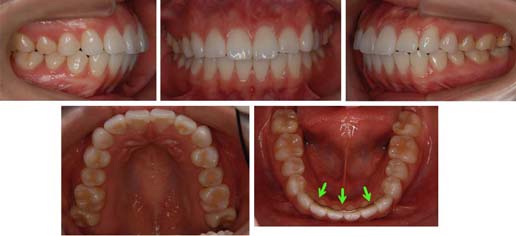

来院時の写真

この患者様はとてもお気の毒な方です。緑色の矢印は固定式保定装置を示しています。一度他の歯科医院で歯を抜かずに矯正治療しました。そのために一見きれいに並んでいますが口もとが飛び出してしまい、上下顎前突になっています。御本人の弁では“猿のような顔になってしまった。何度も改善してくれと訴えたが聞入れてもらえなかった”そうです。最初は歯科に関してかなりの不信感を持たれていました。こんかいは小臼歯を抜歯して治療をおこないました。

実際に上顎の歯列を見ればなんとなくわかってきます。小顔の患者様には不釣り合いなほど歯列が長いです。あれ?少し長くないか?っと思いませんか。実際に長いです。下顎も長いですよね。

歯列弓を見るととても長い感じを受けるはずです。

同じぐらいの倍率にしてみました。上顎の歯列もこんなに小さくなりました。